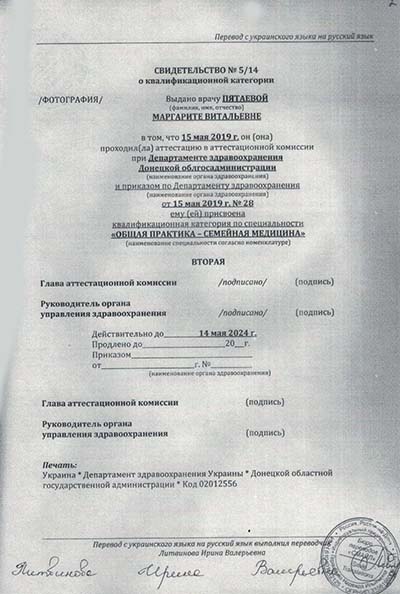

Лицензии и сертификаты

Лечение в нашей клинике анонимно, поэтому никто не узнает, что вы проходите или проходили лечение в нашем наркологическом центре.

Лицензии и сертификаты нашей клиники

Медицинские услуги оказываются ООО "ЮгЭкоСервис+" по лицензии ЛО-61-01-008143 от 28.12.2021 г.